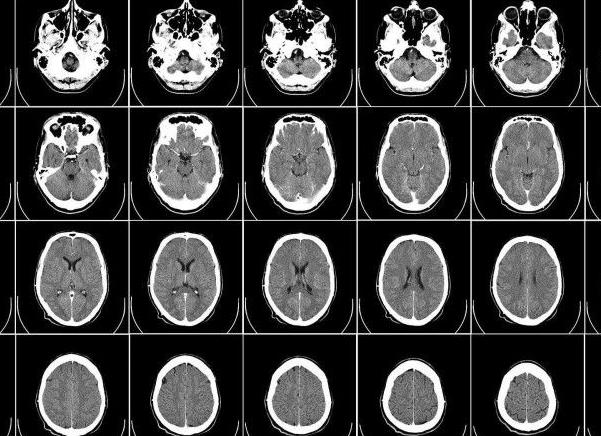

Сам процесс испускание атомами волн фиксируется, и в результате получается снимок. Снимки могут быть выполнены в разной форме. Например, плоскость снимка может быть горизонтальной (поперечный срез головного мозга), профильный (сагиттальный) и т.д.

Что показывает МРТ головного мозга и как проводится томография

МРТ — магнитно резонансная томография — используется для детального изучения головного мозга. Серия снимков, сделанных под действием сильного магнитного поля, позволяет определить состояние тканей и сосудов, выявить наличие новообразований, проследить динамику заболевания и проводимого лечения. Точный ответ на вопрос, что показывает МРТ головного мозга, дает врач радиолог. Вместе с узкопрофильными специалистами он выбирает и метод исследования — обзорную, контрастную, бесконтрастную томографию, ангио- или трактографию.

Что можно увидеть на снимках томографа

Обычный человек может увидеть на изображении мозга совсем немного:

• серый цвет обозначает ткани мозга;

• сероватые прожилки — церебральную жидкость;

• черные пятна сигнализируют об утечке мозговой жидкости;

• белые пятна могут свидетельствовать о наличии опухоли — доброкачественная имеет четкие границы, однородную консистенцию и не пронизана сосудами; злокачественное новообразование имеет размытые очертания.